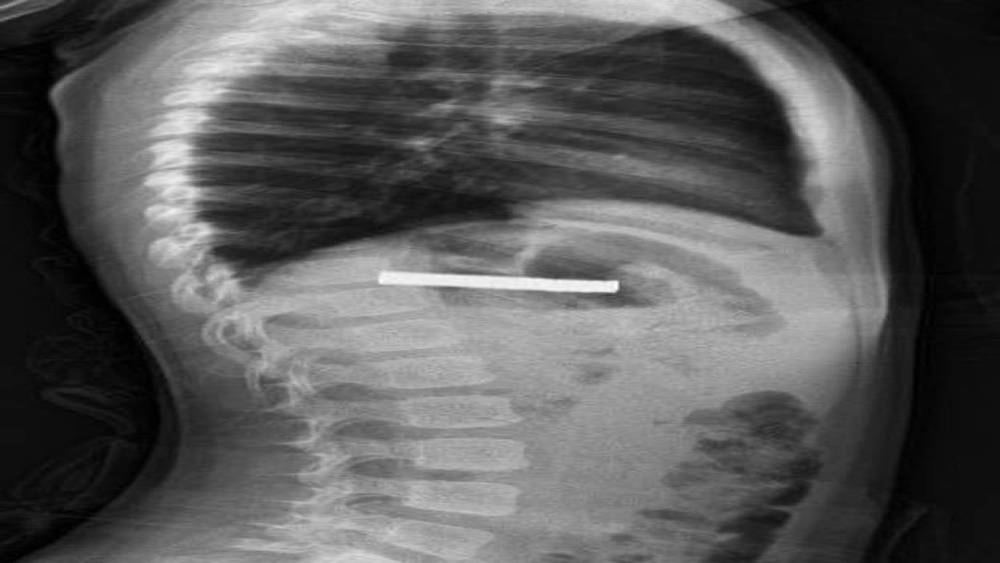

Elazığ’da 3 yaşındaki bir çocuğun yuttuğu 19 mıknatıs, Fırat Üniversitesi Hastanesinde başarılı bir operasyon ile çıkartıldı.

Edinilen bilgiye göre, Erzurum’da bir çocuk evde bulunan 19 tane mıknatısı yuttu. Çocuğun rahatsızlanması sonucu durumu öğrenen aile hastaneye başvurdu. Daha sonra çocuk Elazığ’a sevk edildi. Fırat Üniversitesi Çocuk Gastroenteroloji Hepatoloji ve Beslenme Bilim Dalı Başkanı Prof. Dr. Yaşar Doğan, çocuk hastanın yemek borusuna yapışmış 19 mıknatısı endoskopik yöntemle çıkardı.

Mıknatıslar uzun süre yemek borusunda takılı kaldığı için yemek borusu ve mide girişinde zedelenmeler olurken, çocuğun sağlık durumunun iyi olduğu ve taburcu edildiği öğrenildi.